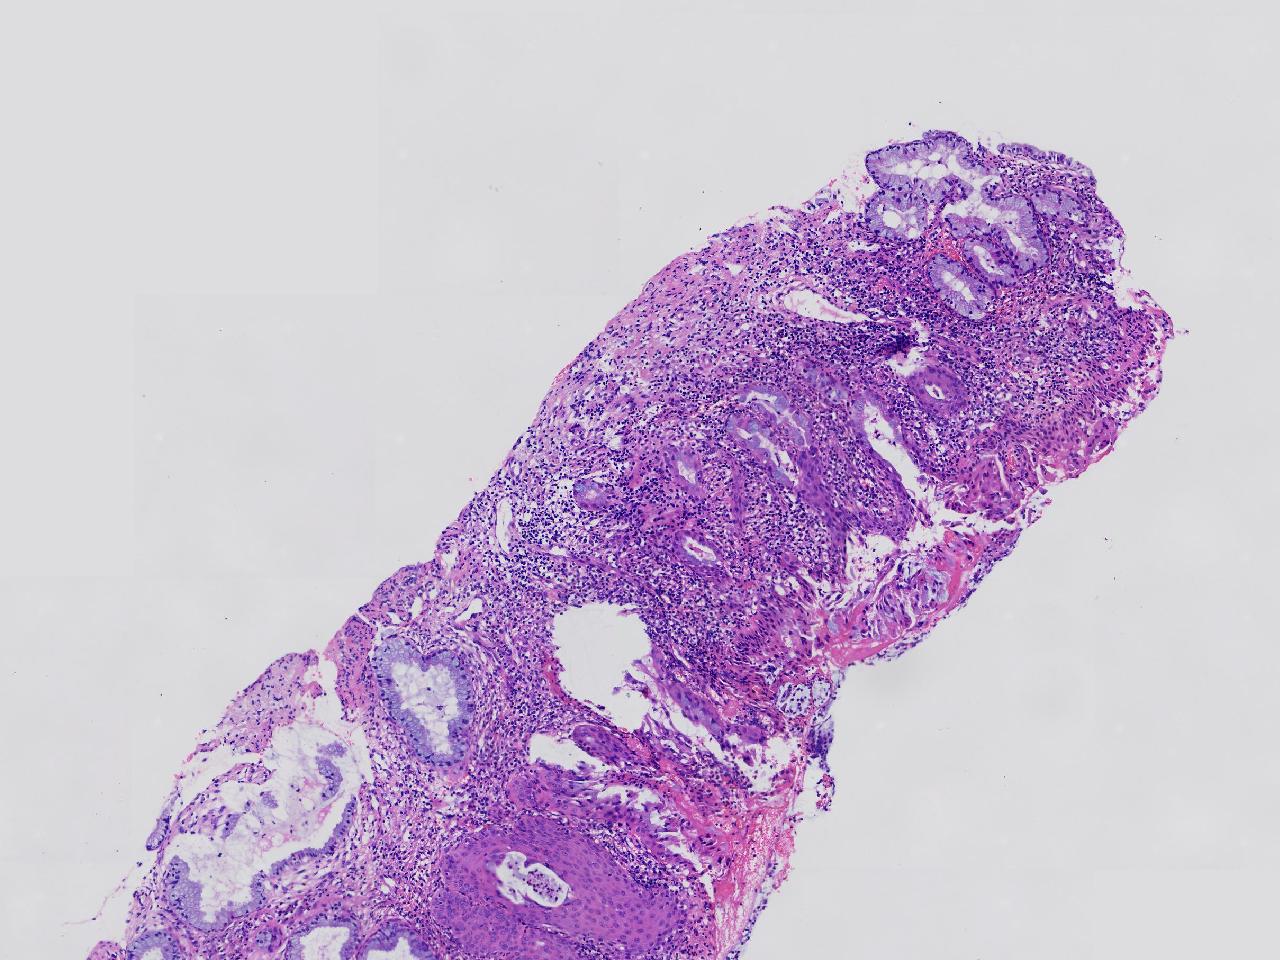

CIN1级? CIN2级?

女,41岁,宫颈活检,HPV16(+)

宫颈多点活检。

灰白色不整形软组织多块。

图1

慢性宫颈炎伴鳞化,建议定期复诊

慢性炎,储备细胞增生伴鳞化,